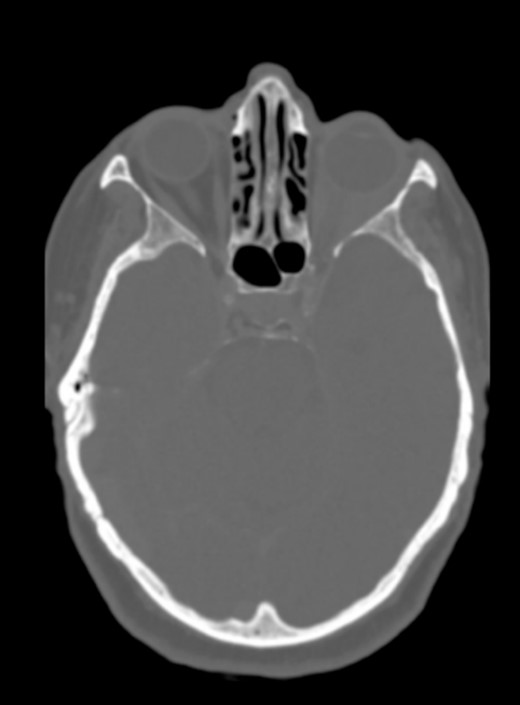

The CT scan displayed a tissue infiltration and bulking of the left superior and lateral extraocular rectus muscle (Fig. 1).

Axial and coronal cerebral CT scans show enlargement of the left lateral and superior rectal muscles (A–B), with slight enhancement (C–D).

There was no evidence of involvement of the central nervous system, and no cranial bone lesions were detected in the CT scan (Fig. 3).